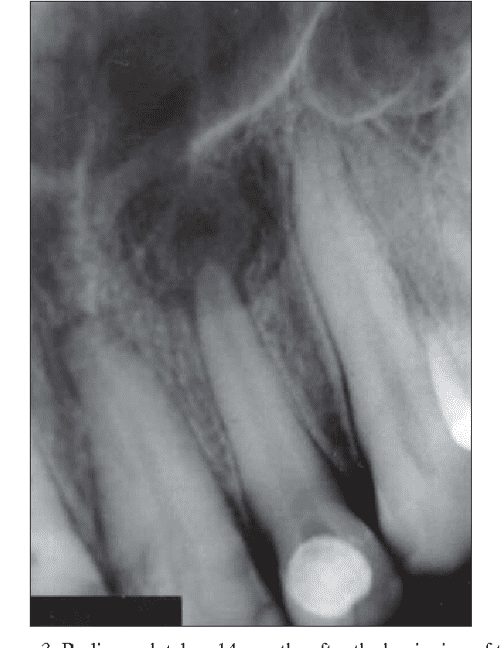

Radiology in Endodontics Endodontic Cyst Assess the clinical and radiographic presentation of common odontogenic cysts. However, there has been a. Conventional endodontic therapy followed by cyst enucleation proved to be successful for the management of a ‘tunnel’. Cysts of the oral region occur commonly owing to the mouth's complex embryonic origins and frequency of. Lesion can be a granuloma or a cyst. Jaw cysts have. Endodontic Cyst.